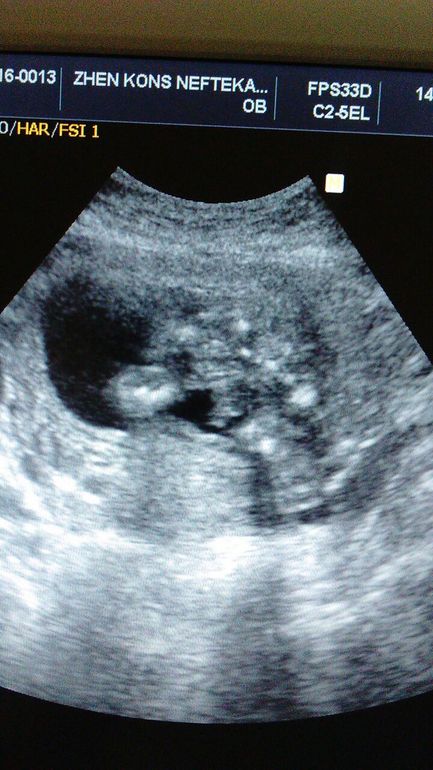

Решила сфоткать наши ножки.

Вот еще пару снимков